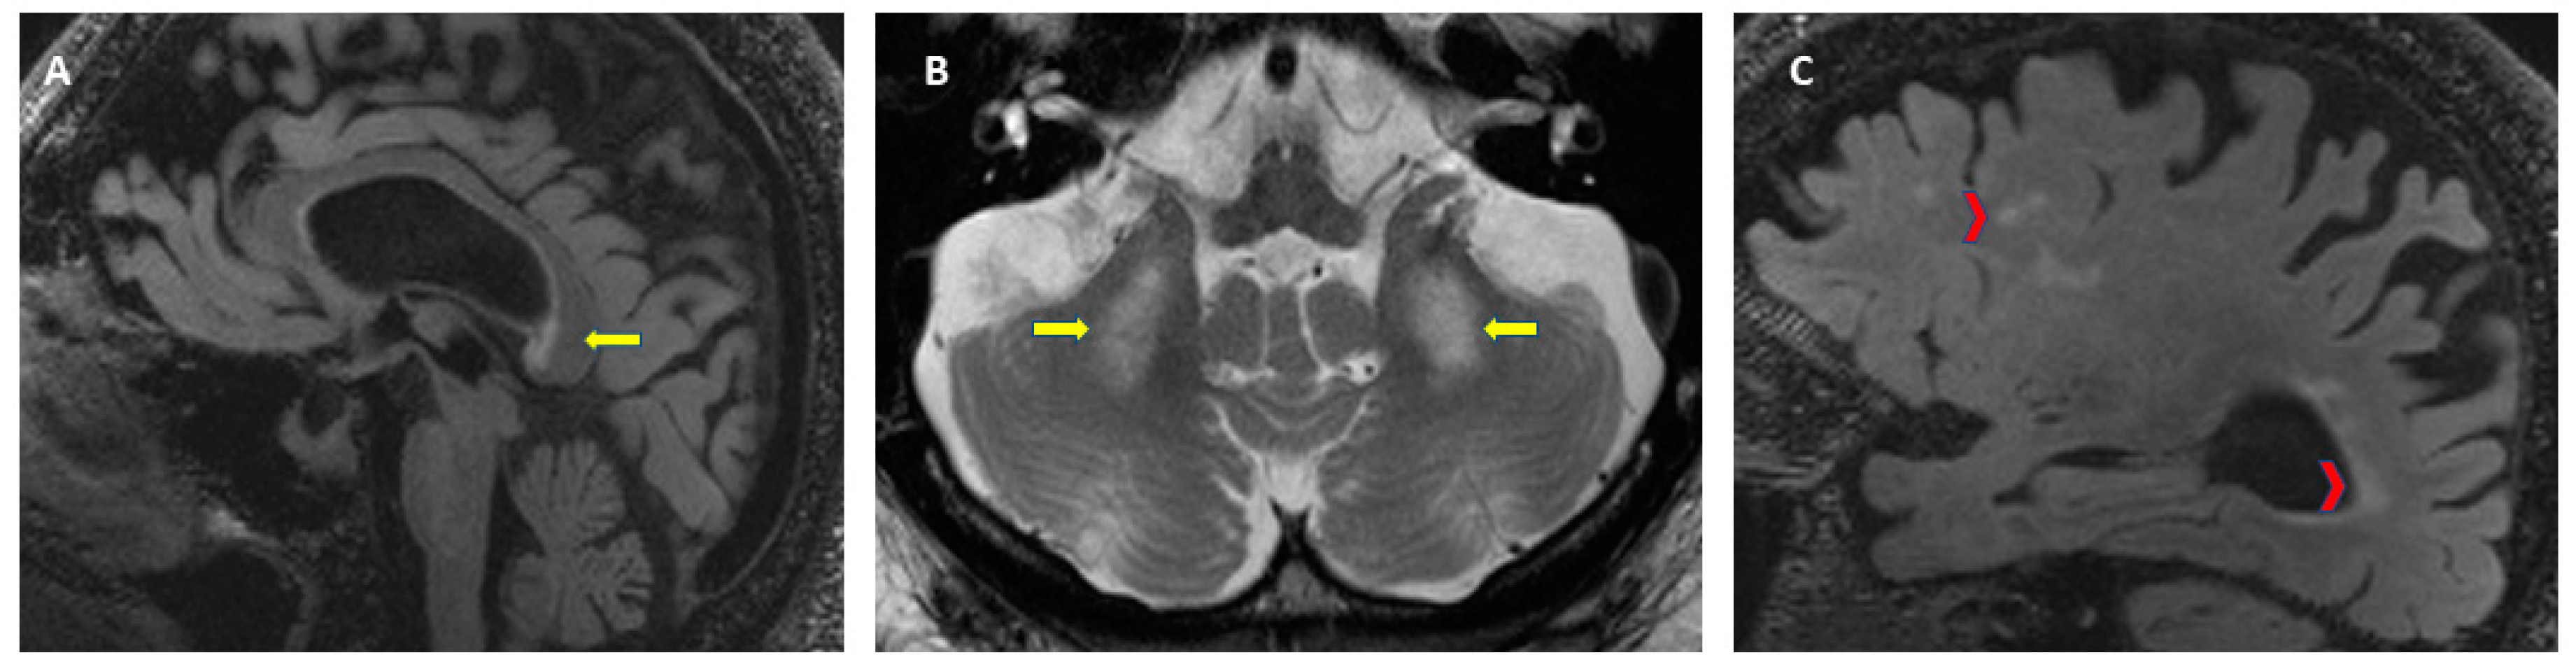

As described earlier, FXTAS is characterized by multiple clinical signs, although there is heterogeneity in the severity depending on the sex of the patient, CGG repeat size, and length of disease. For the diagnosis of FXTAS a molecular diagnosis of an FMR1 gene mutation, including the gray zone, is needed. It is important to know the CGG repeat size since it correlates negatively with the age of onset of symptoms [41] and it correlates positively with the severity of motor signs and brain atrophy [40,154]. The diagnostic criteria for FXTAS were established for the first time in 2003 [18] and later revised in 2014 to expand the radiological and clinical criteria [155]. Due to reports of FXTAS in patients with the gray zone and FM with a lack of methylation or mosaic alleles, the molecular criteria is now considered to be any FMR1 alteration [13,14]. See Table 1 for FXTAS diagnostic criteria and diagnostic categories. When FXTAS is suspected, the clinician needs to perform molecular, clinical, and neuroradiological evaluations. The FMR1 gene testing characterizes the FMR1 mutation, including the gray zone (45 to 54 CGG repeats), which is the only required criteria. A brain MRI allows the evaluation of white matter lesions and brain atrophy; with the presence of white matter lesions in the MCP or brainstem constituting a major radiological sign. These radiological criteria are evaluated on axial flair T2-weighted magnetic resonance images. Figure 4 shows the neuroradiological findings that are part of the diagnostic criteria for FXTAS. A thorough clinical evaluation to assess for intention tremor, cerebellar ataxia, parkinsonism, neuropathy, memory impairment, and executive function deficits is essential for the diagnosis.

Figure 4.

Neuroradiological criteria for the diagnosis of FXTAS. (A) T2-FLAIR: white matter lesions in the splenium of the corpus callosum, (B) T2-TSE: symmetrical white matter lesions in the middle cerebellar peduncles (MCP sign), (C) T2-FLAIR: cerebral white matter lesions and brain atrophy.